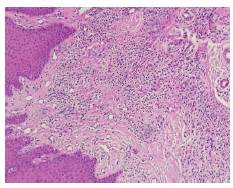

La muestra extirpada se almacenó en formol tamponado al 10 % para su análisis histopatológico (figura 4A). Esta arrojó el siguiente resultado: los cortes mostraron mucosa oral con hiperplasia marcada del epitelio. A nivel de la lámina propia se observó infiltrado inflamatorio de predominio linfoplasmocitario de distribución heterogénea, proliferación fibrocolágena y de vasos de pequeño calibre (figura 4B) El diagnóstico definitivo es granuloma telangiectásico.